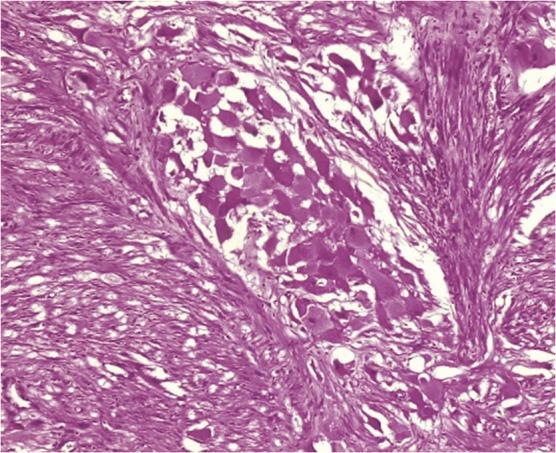

Primary simultaneous multiple organs teratomas are extremely rare. They usually arise in the gonads, and only 1-3 % of them arise in the mediastinum. We present a case of simultaneous multiple organs immature teratomas who was admitted to Razi hospital because of cough, dyspnea, and left-side supraclavicular mass. Computed tomography (CT) showed a big mass with multiple high densities, nodular, semi-solid, heterogenic structures on the left side of the neck, left-side anterior mediastinum, right-side middle mediastinum and right-side suprarenal region. CT-guided needle biopsy was performed and histopathological study showed immature teratoma. After performing neoadjuvant therapy, the tumors were removed. The patient underwent chemo radiation therapy on the mediastinum and abdomen. On 6-months follow-up, he was asymptomatic. This case is being reported because of the rarity of multiple organs immature teratomas and informing other clinicians about managing these cases.

原发性同时性多器官畸胎瘤极为罕见。它们通常起源于性腺,其中仅有1% - 3%起源于纵隔。我们报告一例同时性多器官未成熟畸胎瘤病例,该患者因咳嗽、呼吸困难及左侧锁骨上肿块入住拉齐医院。计算机断层扫描(CT)显示,在颈部左侧、左侧前纵隔、右侧中纵隔及右侧肾上腺区域有一个巨大肿块,具有多个高密度、结节状、半实性、异质性结构。进行了CT引导下针吸活检,组织病理学研究显示为未成熟畸胎瘤。在进行新辅助治疗后,切除了肿瘤。患者接受了纵隔和腹部的放化疗。在6个月的随访中,他没有症状。报告此病例是因为多器官未成熟畸胎瘤罕见,并向其他临床医生通报此类病例的处理方法。